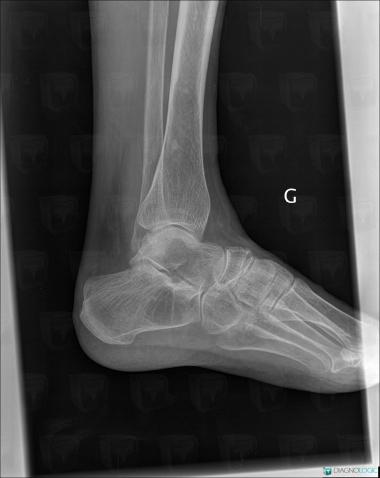

Avascular necrosis, Tibia - Distal part, X rays

Here is the specific information in the key image above:

- Diagnosis Avascular necrosis, Location(s) Tibia - Distal part, with gamuts Well-defined osteolysis

Avascular necrosis, Talus, Calcaneus, X rays

- Diagnosis Avascular necrosis, Location(s) Calcaneus, with gamuts Lucent lesion in footTalus, with gamuts Lucent lesion in foot